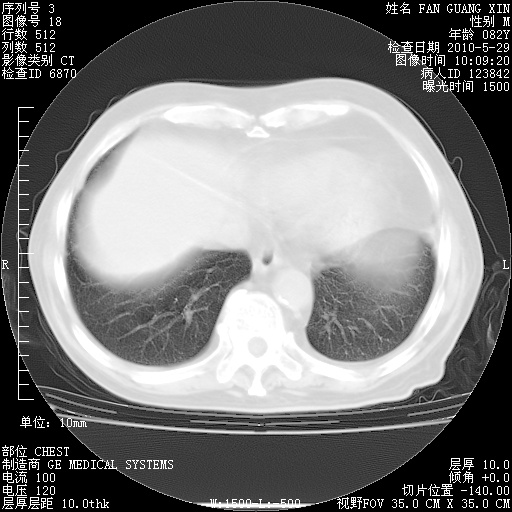

再治疗10天后的肺部CT

肺部体征:呼吸25次/分,心率100次/分,呼吸音增粗。无干湿罗音。

从白细胞总数和中性比例看好像合并感染。肺部纹理好像比上次多,支气管炎?其他感染?

阅读此次胸部CT,肺间质渗出性改变较入院时有吸收。目前从体温、白细胞、中性分叶明显增高,肯定存在细菌感染(发生医院感染哦,若无消化道及泌尿系统等感染的依据,肺部感染可能大)。若你院头孢哌酮舒巴坦钠耐药率较高,同意你的方案,若48小时体温仍高,可考虑使用碳青霉稀类抗菌药物,同时可予超声雾化、注意滴数时加大液体量。白蛋白33.30g/L较低哦,需加强营养等支持治疗。